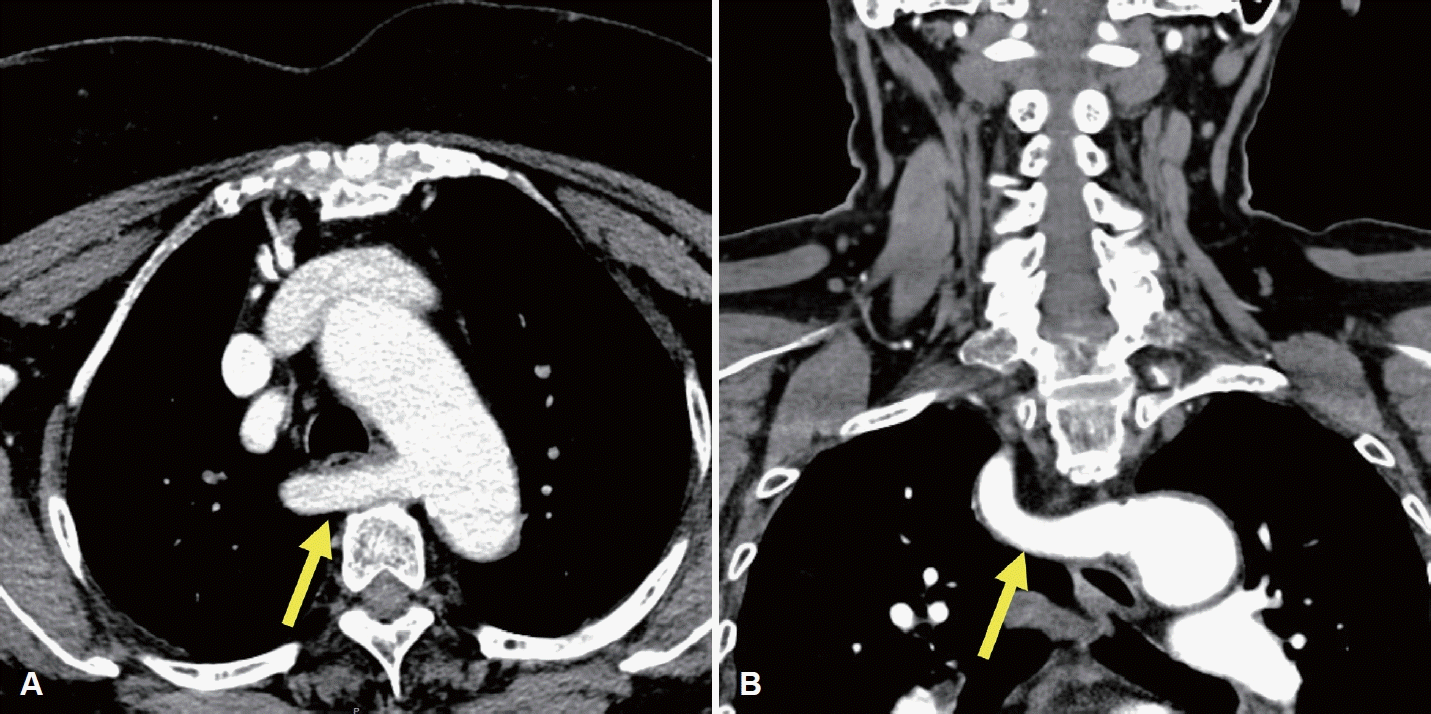

Fig. 1.

Preoperative enhanced thyroid CT images of an ARSA. A: Axial enhanced CT shows the ARSA (arrow) arising from the aortic arch and coursing posterior to the esophagus. B: Coronal enhanced CT shows the retroesophageal ARSA (arrow). ARSA, aberrant right subclavian artery.